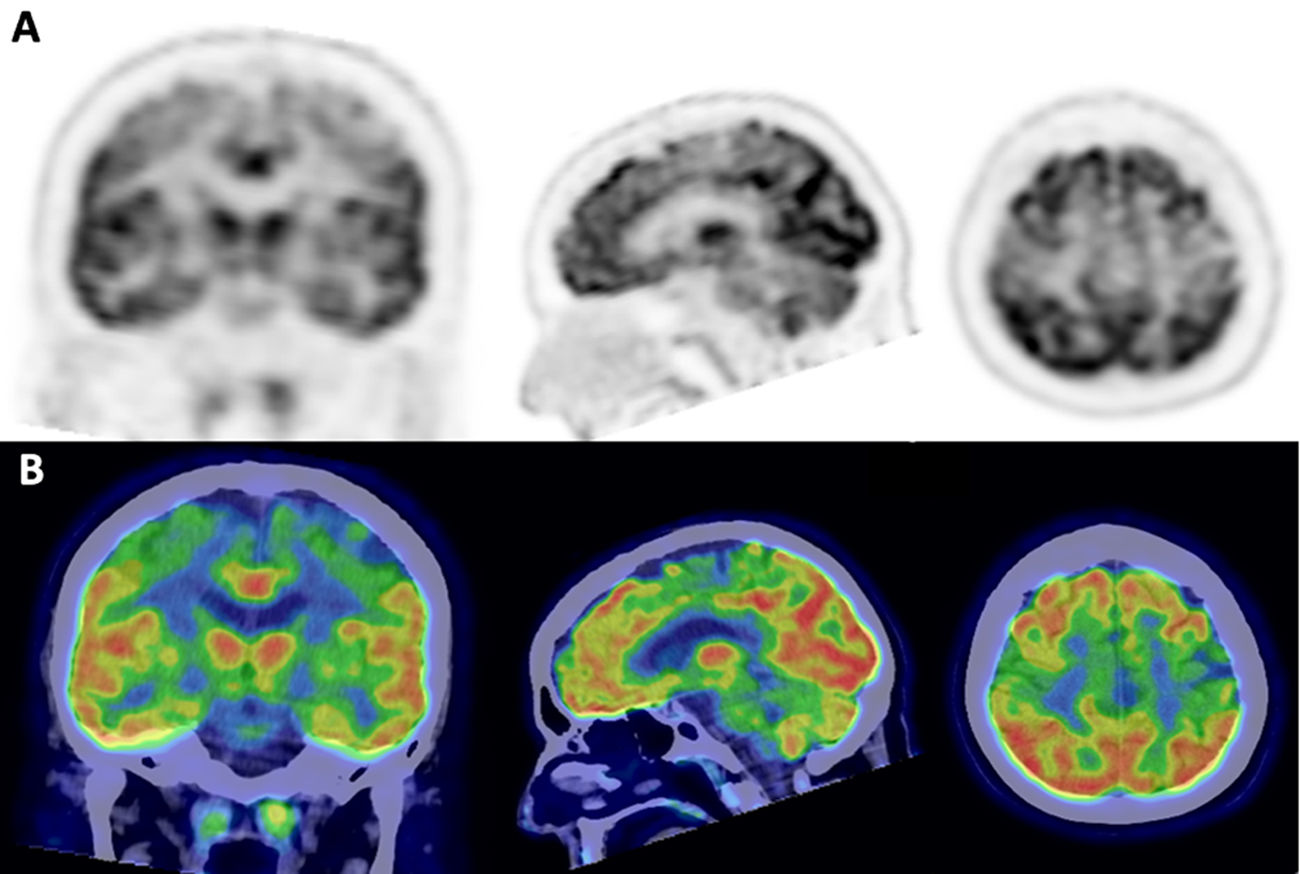

Signo de la banda motora en el PET/TC 18F-FDG cerebral: ¿un biomarcador de enfermedad degenerativa de primera motoneurona? A propósito de 3 casos y revisión de la literatura

Introducción Las enfermedades de motoneurona (EMN) incluyen afecciones como la esclerosis lateral amiotrófica (ELA) y la esclerosis lateral primaria (ELP), caracterizadas por la degeneración progresiva de la primera y/o segunda motoneurona. La identificación de biomarcadores […]